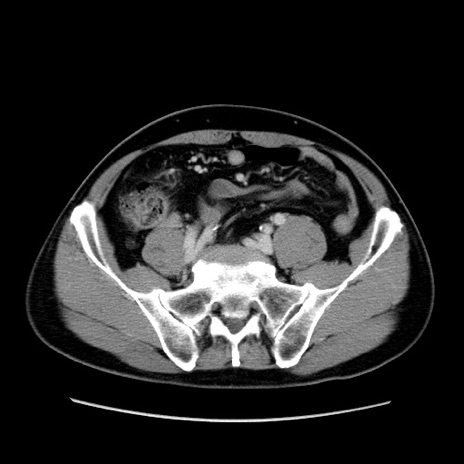

症例34(横断像)

【症例】60歳代 男性

【主訴】右鼠径部膨隆

【現病歴】1年程前より右鼠径部膨隆あり。自己にて還納可能だったため放置していた。3時間前より右鼠径部の脱出を認め、還納困難となり受診。

【既往歴】高血圧

【身体所見】右鼠径部に小児頭大の膨隆あり。弾性硬であり、用手還納は困難。左鼠径部にも膨隆を認める。脱出はなし。